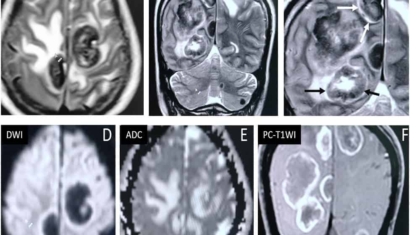

52 year old man with no co-morbidities presented with history of generalised seizures .